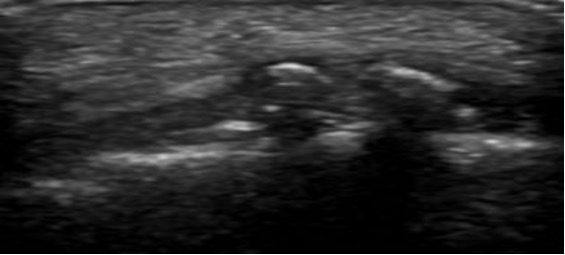

- Bursa retrocalcânea: Distensão anecoica ou hipoecoica (acúmulo de líquido).

- Bursa superficial/subcutânea: edema hipoecoico entre a pele e o tendão. Ambas as estruturas podem parecer aumentadas e inflamadas.

- Convexidade dos tecidos moles posteriores ao tendão (bursite superficial).

A ultrassonografia é uma modalidade altamente eficaz para avaliar ou diagnosticar a deformidade de Haglund e a síndrome de Haglund, além de auxiliar na definição de patologias ósseas e de tecidos moles ao redor da inserção do calcâneo. Os principais achados incluem uma protuberância calcânea posterossuperior, tendão espessado e hipoecoico, bursite retrocalcânea e superficial e aumento do fluxo Doppler em casos de inflamação ativa.